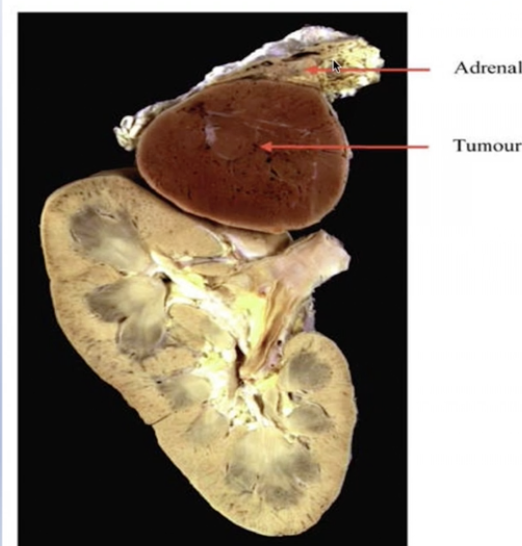

Pheochromocytom

Diagram shows andranergic tumour (tumour on the adrenal gland) releasing adrenaline into the circulation causing vasoconstriction and hypertension.

adrenal is in the region of the kidneys but it is not considered a renal disease.